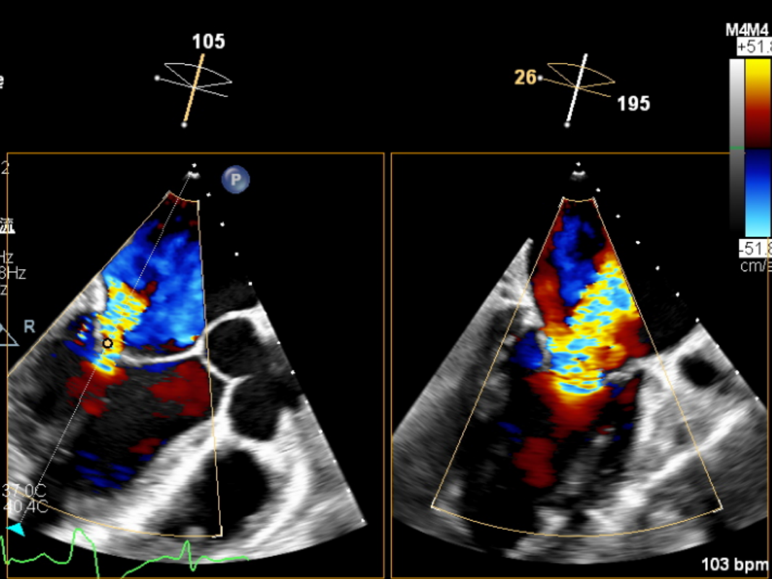

手术过程:手术采用经右侧股静脉入路,在TEE和DSA引导下完成房间隔穿刺,位置偏后偏上,穿刺高度为3.9厘米。置入瓣膜夹系统后,在左房调整瓣膜夹的轴向(orientation)和前进轨迹(trajectory),后进入左室进行瓣叶抓捕。由于两个瓣叶无法对合,后瓣叶较短,在尝试同时抓捕几次后,决定使用单独抓捕功能。先抓捕前瓣叶,再抓捕后瓣叶,确认瓣叶插入长度足够,缓慢关闭瓣膜夹。即刻返流程度降至轻度,跨瓣平均压差为2mmHg,最终成功释放瓣膜夹。采用“8”字缝合法关闭股静脉入路。术后肺静脉逆流和左房压都明显好转,预示着良好的预后。手术共耗时2小时,术后患者无明显不适,安返CCU继续观察。

术后TEE(≤1+)